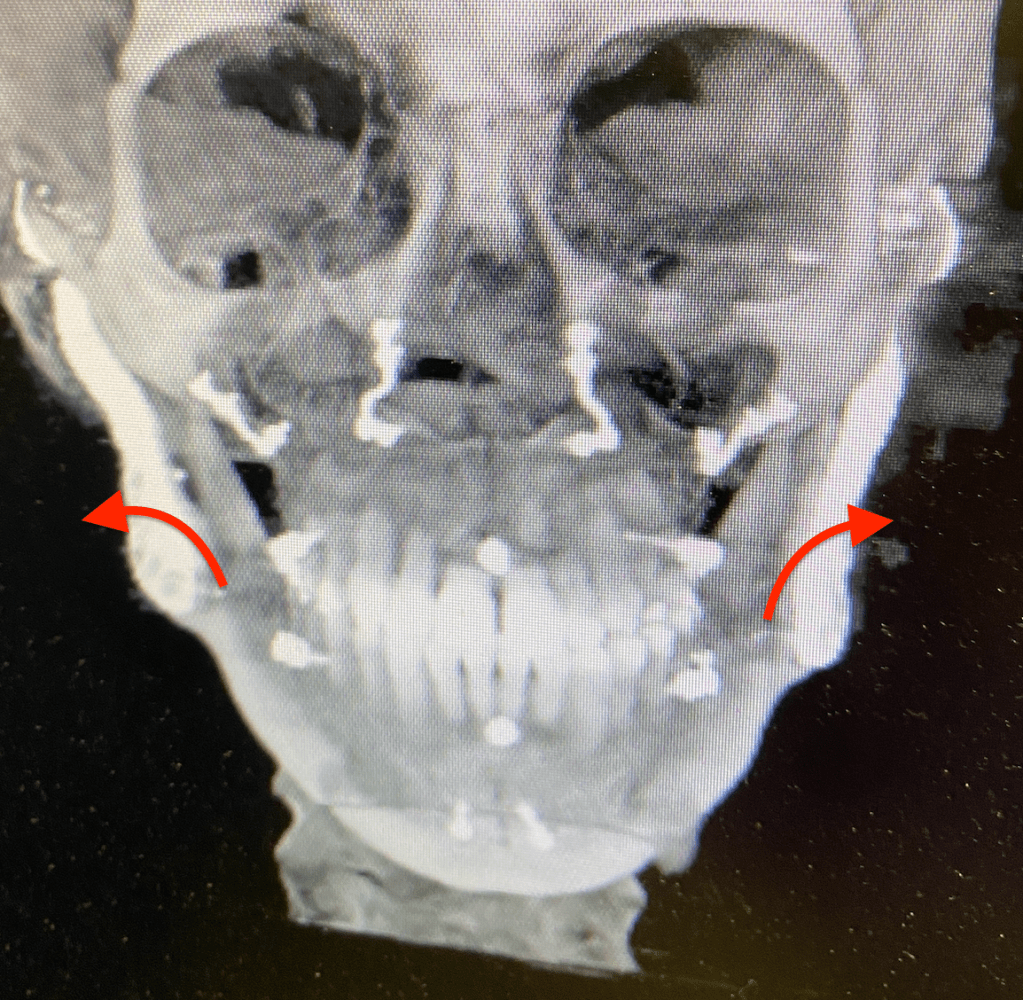

- Past pain patterns: My old pain patterns are STILL not presenting themselves!! I am so happy about this!!!!!! I figured out now that I am on the other side of this, that my MANDIBLE was pressing hard on all my neck muscles, it was so far back on my neck from losing the 75% of my condyles on both side over the last 20 years. It was probably causing most of my radiating pain in the final years. Joint pain was starting to get worse as well, but it wasn’t as “searing” as it was in 2016 before my fat graft diskectomies.

- I have noticed more and more than the right side of my bite meets but not the left. I will definitely need some work once I can get my mouth opening up to 30mm is the goal, I am hoping for a more normal 38-40mm if I can. Normal jaws can usually open 40-45mm if I remember correctly. (right now I can only open 10mm, enough to squeeze a pill or force a baby toothbrush in). I try and open my mouth and let the lower jaw hang to try and stretch out these muscles, I still have not been given any exercises officially though. Maybe next appointment with my surgeon we will discuss this

- Have a zoom appointment with my orthodontist next week as well where I plan to talk to him about the concerns on my bite and my concerns over the scanning device they use in their office, I had trouble fitting it in my mouth even when I could open wider. I worry that it might have trouble fitting into my mouth. I would NEVER want them to force it as I always have to be gentle on the joints, they run the risk of popping out of the socket although rare, would require surgery to pop it back in or most likely a new joint would have to be ordered. I really hope that Stryker/TMJ Concepts waiting list goes from 6 months to 3 months real quick!